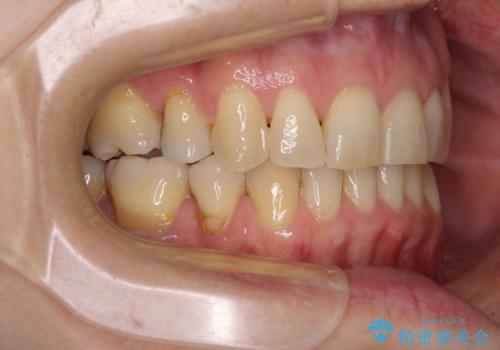

インビザライン・ライトは、製作できるアライナーの枚数に制限があるため、移動可能な量に限りがあります。

軽微な後戻りの治療であったため、十分に治療を行うことができました。

口を開けたときに金属が見えなくなり、患者様には大変満足していただきました。